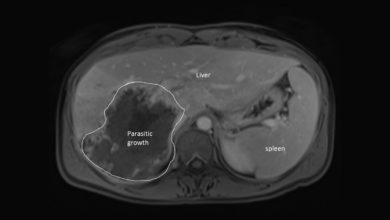

Supplied by Stan Houston Rare liver parasite gradually affecting more Albertans

While public health concerns have centred on the coronavirus lately, the spread of a rare parasite has been on the…